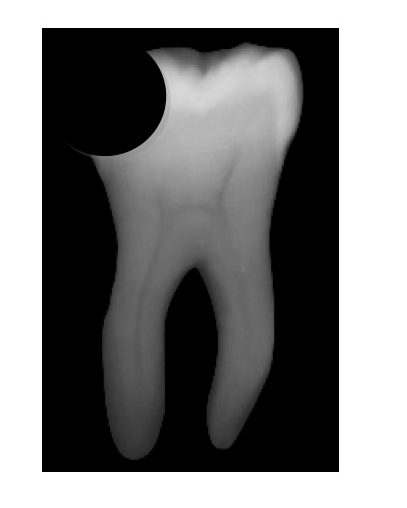

歯は骨に刺さっており、そこから栄養を取って大きくなったり、虫歯から身を守ったりしているのですが、その栄養をとる歯の根っこから伸びる管のことを「根管(こんかん)」といいます。

レントゲンで見るとよくわかるのですが、レントゲンの真ん中にある黒く細いひも状のものが神経が入っている「根管」です。

進行した虫歯はこの「根管」にまで影響を及ぼし、感染が根の先端にまで進むと、既に神経のない歯でも酷い痛みや腫れが生じるようになります。そうなった場合、根管をきれいに掃除して感染物質を除去する「根管治療」が必要になります。